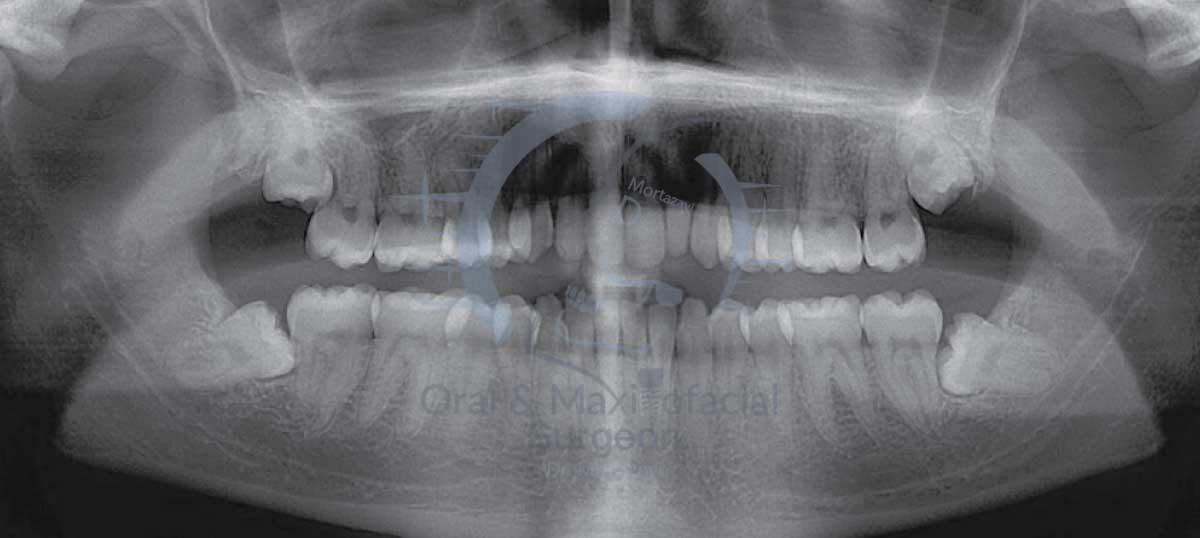

قبل از هر اقدامی، دندانپزشک شما را معاینه کرده و یک عکس رادیوگرافی (مانند OPG) از فک شما تهیه میکند. این عکس به دندانپزشک کمک میکند تا وضعیت دقیق دندان عقل، ریشه آن، و نزدیکی آن به عصبها یا حفرههای سینوسی را ارزیابی کند. در این مرحله، تمامی گزینههای درمانی و خطرات احتمالی با شما در میان گذاشته میشود. توجه کنید درصورتی که دندان عقل نهفته باشد حتماً میبایست تصویر cbct نیز تهیه شود. این تصویر محل دقیق ریشه دندان عقل را مشخص میکند و از عوارضی مانند بیحس شدن لب که ممکن است بعد از کشیدن دندان عقل به وجود بیاید، جلوگیری میکند.

در واقع، دندانهای عقل بقایای تکاملی نیاکان ما هستند که فکهای بزرگتری برای جویدن غذاهای سفت و خام داشتند. اما امروزه با تغییر رژیم غذایی و کوچکتر شدن فک انسان، اغلب فضای کافی برای رویش صحیح این دندانها وجود ندارد. مشکلات رایج ناشی از دندان عقل، اغلب به دلیل نهفتگی (Impaction) است. نهفتگی به حالتی گفته میشود که دندان به صورت کامل یا جزئی در زیر لثه یا استخوان فک گیر میکند و نمیتواند به درستی بیرون بیاید. این نهفتگی خود انواع مختلفی دارد که هر کدام مشکلات خاص خود را ایجاد میکنند:

- نهفتگی افقی (Horizontal Impaction): این نوع نهفتگی یکی از خطرناکترین انواع است. دندان عقل به صورت کامل به پهلو خوابیده و به ریشه دندان مولر دوم فشار میآورد. این فشار میتواند باعث تخریب ریشه و پوسیدگی دندان مجاور شود.

- نهفتگی زاویهدار (Angled/Mesial Impaction): در این حالت، دندان عقل با زاویه به سمت دندان مجاور رشد میکند و به آن فشار وارد میکند. این شایعترین نوع نهفتگی است.